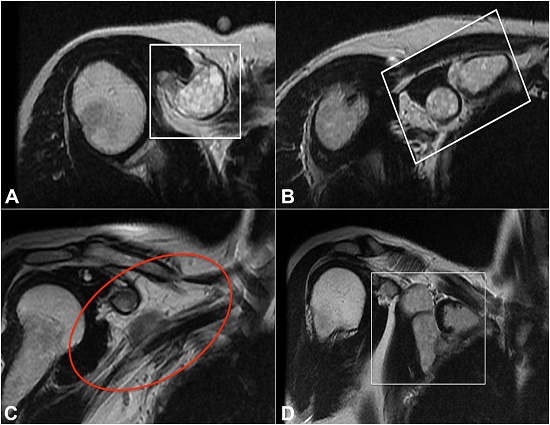

The magnetic resonance imaging (MRI) of the shoulder confirmed a soft-tissue tumor affecting the pectoralis minor, which measured 6.3x4.4x1.6 cm. The mass was delimited by the muscular aponeurosis, preserved the brachial plexus; and cranially reached the coracoid process. The lesion showed a thin and well-defined margin except for its posterior and cranial margin, showed hyperintense signal in T2 weighted images, and no contrast enhancement was observed. These findings were consistent with a vascular malformation of lymphatic origin (cystic lymphangioma) ( Figure 2).